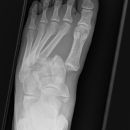

Metatarsale 5